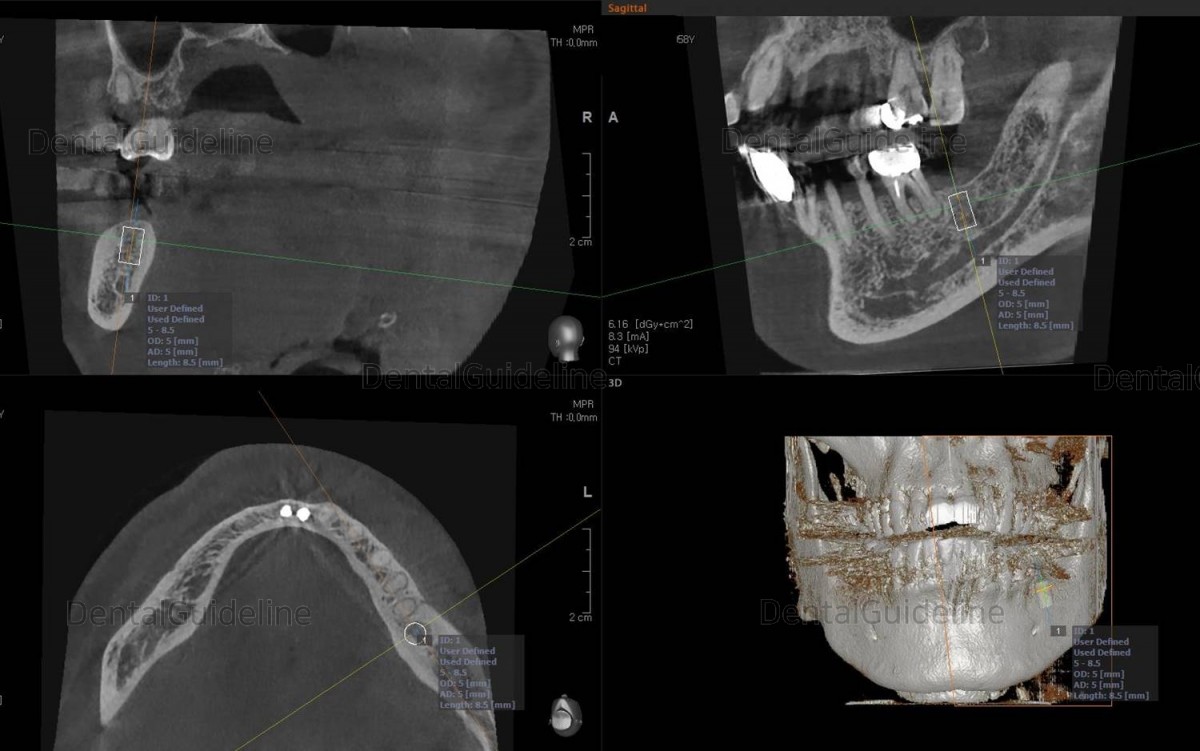

Post-op CBCT.

About 3.5 months after the placement of the implant.